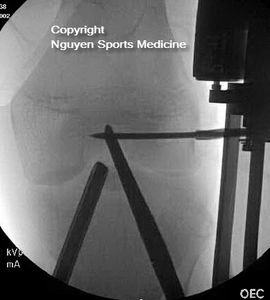

- Pediatric ACL Surgery